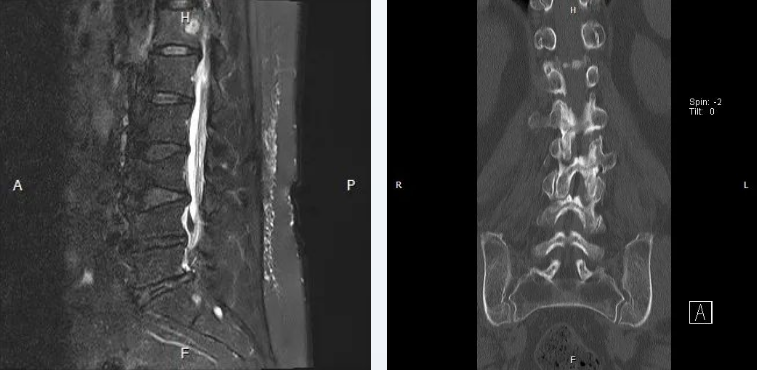

住院后,神经外科程扬主任精心为患者进行细致查体,并完善了腰椎CT及腰椎核磁共振等检查;最终患者被初步诊断为:腰椎间盘突出,继发椎管狭窄。

随后,王贵怀教授与程扬主任制定了详细的手术方案,拟在显微镜下行后路腰4-5扩大椎管减压、神经根管减压术。术程顺利,术中通过彻底磨除腰4、腰5、骶1椎骨左侧椎板,来达到减压效果。术后,困扰患者2年多的症状得到了明显好转。